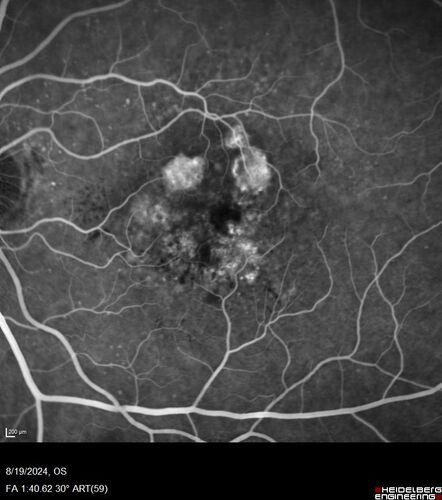

Wet AMD - Occult CNVM and Geographic atrophy

77 year old female with mild vision loss - 20/32 - responded to Avastin

Occult CNVM wet AMD and Geographic Atrophy